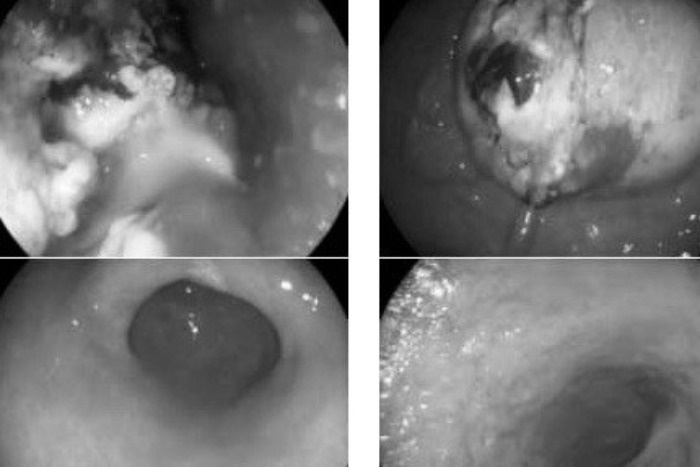

Hình ảnh tổn thương thực quản qua ống nội soi của bệnh nhân. Ảnh: BSCC.

Lần thứ 3 đến khám, bác sĩ Thành cho biết bệnh nhân gầy, sút cân nhiều, ăn uống khó khăn, gần như không thể ăn được thức ăn đặc, cơ thể ốm yếu. Khi nội soi, các bác sĩ thấy khối u đã to lên chiếm gần hết lòng thực quản, dây soi qua khó khăn. Các hạch cũng tiếp tục phát triển. Dạ dày bệnh nhân cũng có vết loét. U dạ dày đã được sinh thiết và cùng nguồn gốc với u thực quản.